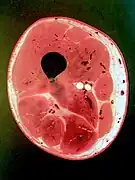

Photo of cross-sectional slice from a plastinated human thigh.

Schematic drawing of a transverse section of the thigh illustrating its fascial anatomy.